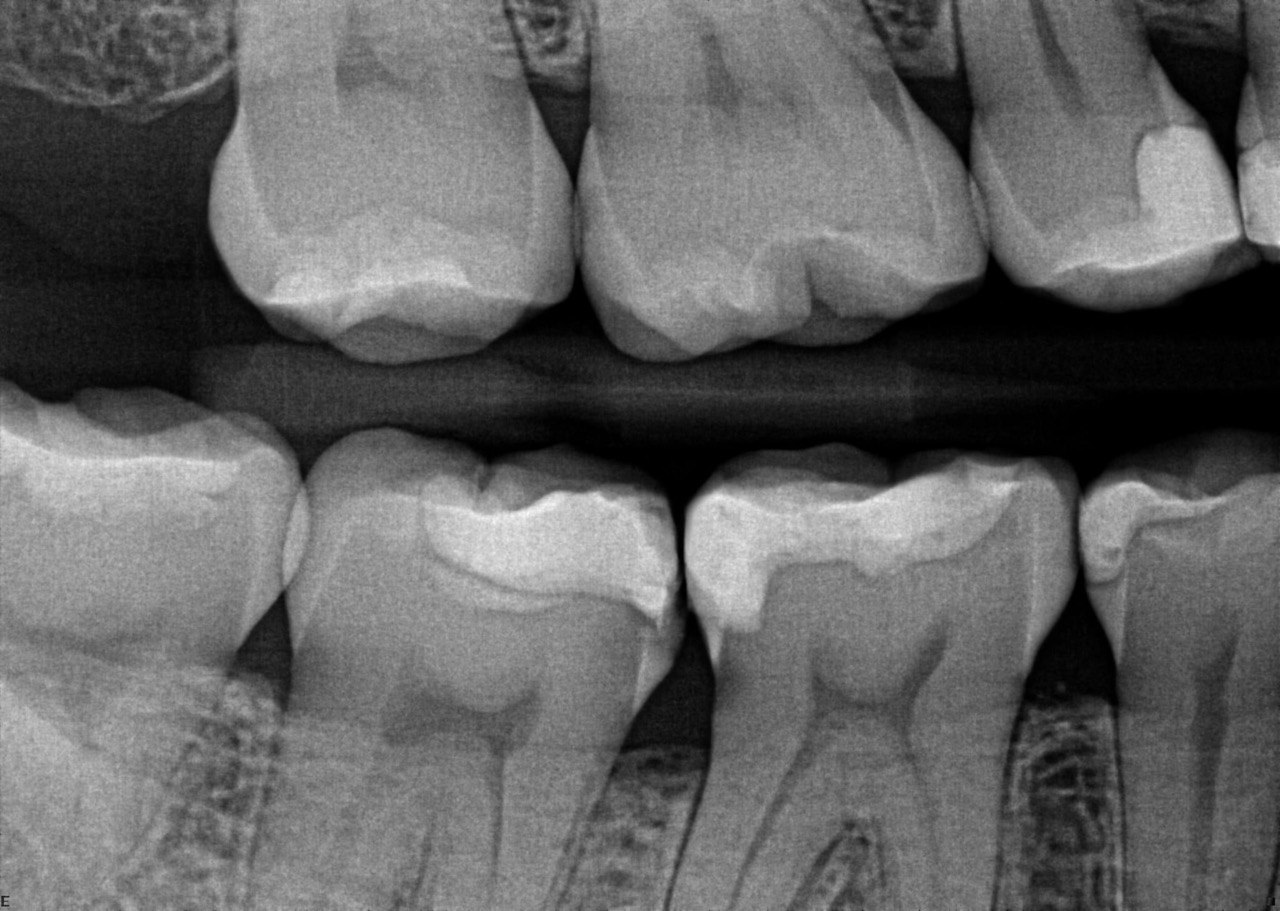

24. What condition can be seen on the distal surface of the tooth # 3.7?

25. What condition can be seen on the mesial surface of the tooth # 3.5?

26. What condition can be seen on buccal surface of the teeth # 2.3,2.4,2.5?

27. What condition can be seen on the distal surface of the teeth # 4.3 and mesial surface of 4.4?

28. What condition can be seen on buccal surface of the teeth # 1.1 and 2.1?

29. What condition can be seen on mesial surface of the tooth # 3.6?

30. What condition can be seen on mesial surface of the tooth # 3.4?